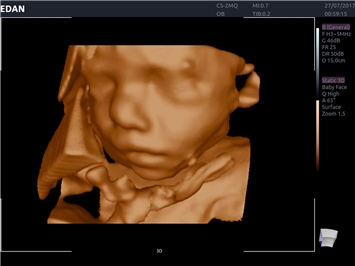

• 3D/4D-визуализация с автоматическим редактированием объема (eFace)

• Акушерства и гинекологии

3D/4D:

Да